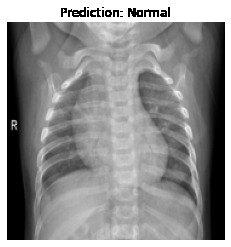

Currently, there is an urgent need for efficient tools to assess the diagnosis of COVID-19 patients. In this project, we propose a constructive solution for detecting and labeling infected tissues on CT lung images of such patients. To cut down false positives our model is trained on 4 types of lung CT images : COVID, Viral Pneumonia, Lung Opacity and normal images to get the best possible results with highest accuracy.

We built it using Tensorflow 2.x using Python. We have developed a Convolutional Neural Network model with an average accuracy of more than 85%.

We are proud that among the top 5 models, one of our models achieved 88.8% accuracy with very low loss.

We learned that COVID-19 can be succesfully detected through LUNG-CT images instead of tedious tests like Reverse transcription polymerase chain reaction (RT-PCR) which takes almost 5 hours and Rapid detection tests which has a low accuracy.

Our model contains the best of both worlds with quick detection and high accuracy.